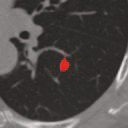

Deep learning based medical image segmentation models usually require large datasets with high-quality dense segmentations to train, which are very time-consuming and expensive to prepare. One way to tackle this challenge is by using the mixed-supervised learning framework, in which only a part of data is densely annotated with segmentation label and the rest is weakly labeled with bounding boxes. The model is trained jointly in a multi-task learning setting. In this paper, we propose Mixed-Supervised Dual-Network (MSDN), a novel architecture which consists of two separate networks for the detection and segmentation tasks respectively, and a series of connection modules between the layers of the two networks. These connection modules are used to transfer useful information from the auxiliary detection task to help the segmentation task. We propose to use a recent technique called "Squeeze and Excitation" in the connection module to boost the transfer. We conduct experiments on two medical image segmentation datasets. The proposed MSDN model outperforms multiple baselines.